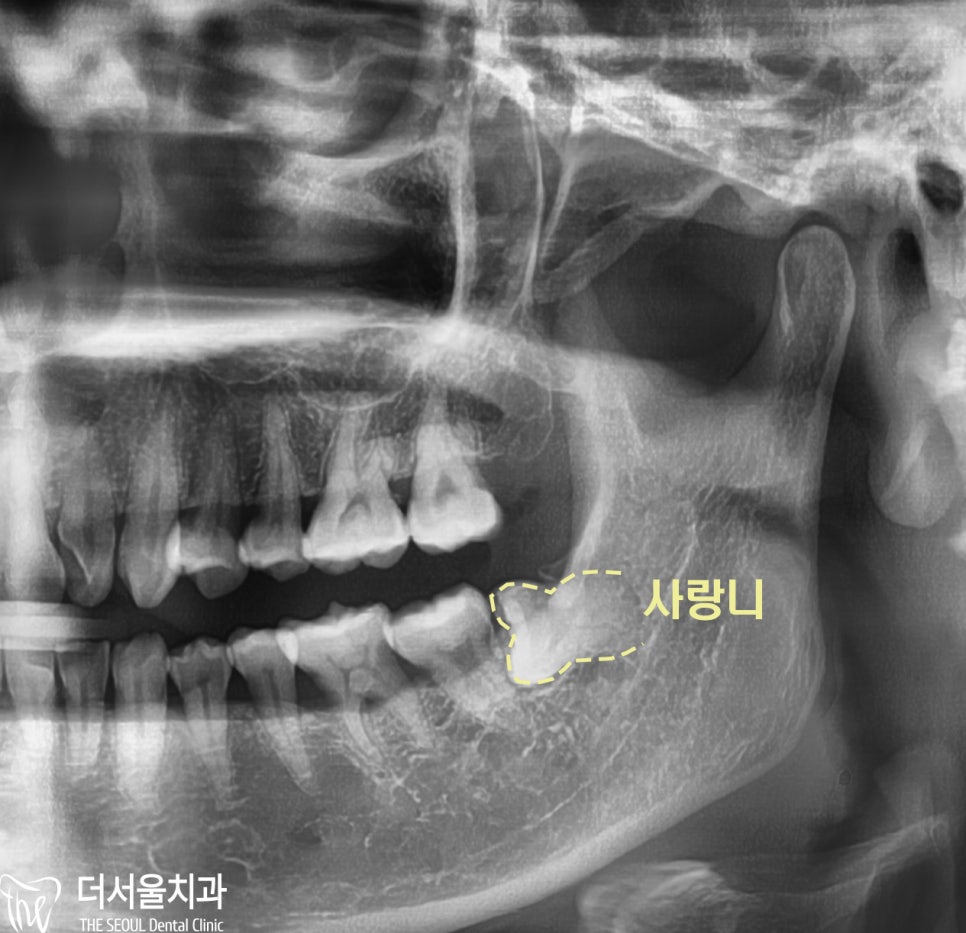

파노라마 엑스레이를 찍어보게 되었고

제 3대구치가 누워서 자란 것을 볼 수 있었습니다

사랑니가 잇몸 속에 묻혀 있는 것으로 모자라

옆으로 누운 형태로 맹출했는데 방향이 좋지 못해서

발치 가 꼭 필요한 상황이었습니다.

더군다나 아래턱에 위치한 신경관과

사랑니 의 거리가 가까워 보였기 때문에

3D-CT 촬영으로 정밀 진단을 하게 되었는데요.